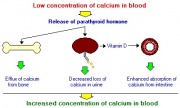

| 17:46, 26 במאי 2013 | הורמוןפ2.jpg (קובץ) |  |

17 קילו־בייטים | Nachi | 1 | |

| 17:46, 26 במאי 2013 | הורמוןפ1.jpg (קובץ) |  |

36 קילו־בייטים | Nachi | 1 | |

| 17:40, 26 במאי 2013 | הורמון2.jpg (קובץ) |  |

22 קילו־בייטים | Nachi | 1 | |

| 17:40, 26 במאי 2013 | הורמון1.jpg (קובץ) |  |

15 קילו־בייטים | Nachi | 1 | |